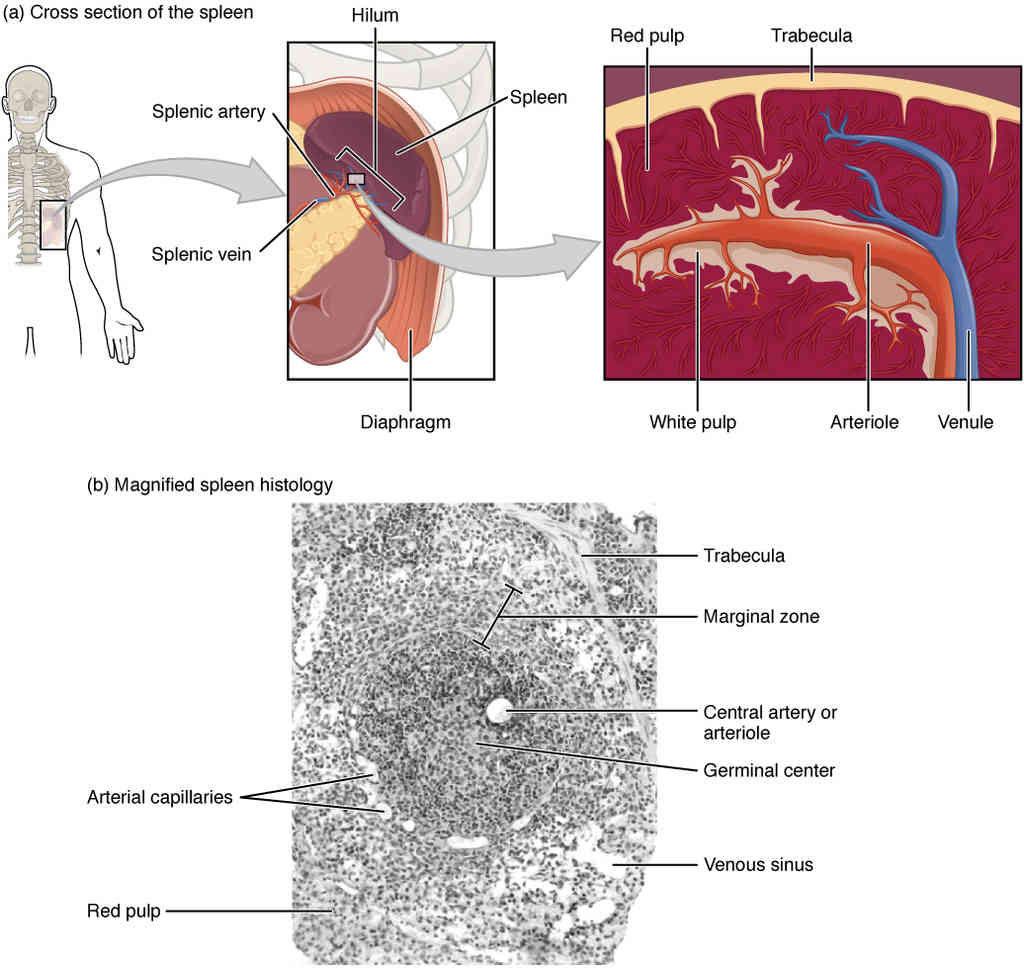

This page is under construction. For now, it is just a resource of the images found in the OpenStax Anatomy and Physiology Handbook. It wil slowly change into a revision tool. Each slide has a number. Use this to refer to the slide. When completed, it will have an unlabelled section, with labelled slides in parallel. On the unlabelled slides, write your answer and use the labelled slide to assess yourself. Keep track by also noting the number on each slide. Improvement at each attempt is important, more so than full marks on a first attempt.